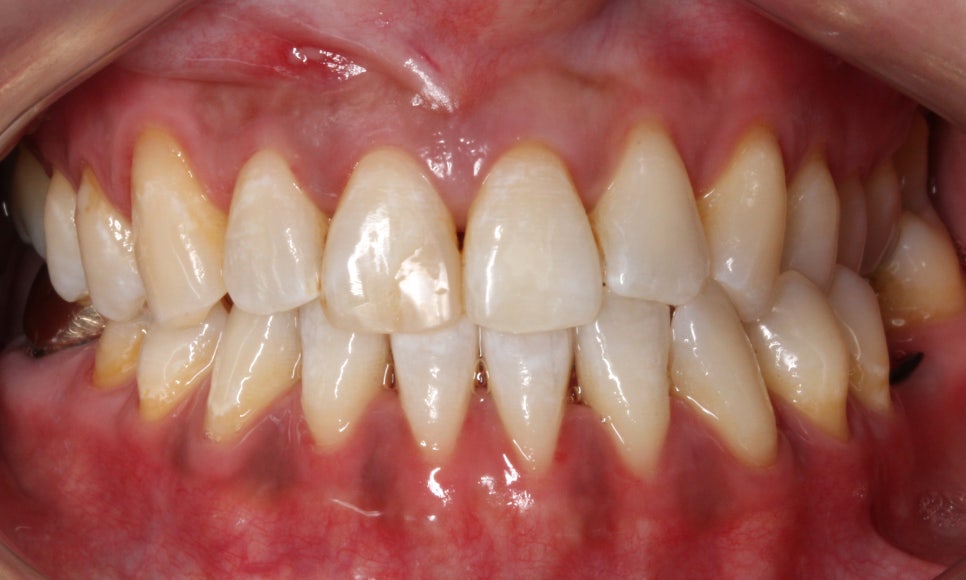

□ 앞니 벌어짐

출처:투디치과/ 앞니 벌어짐 사례의 블링스 전후 사진입니다.

전, 후 사진의 전 사진을 보시면

치아 사이가 벌어져있는 모습을 보실 수 있습니다.

블링스로 어색하지 않은 자연스러운 앞니로 개선됐네요!